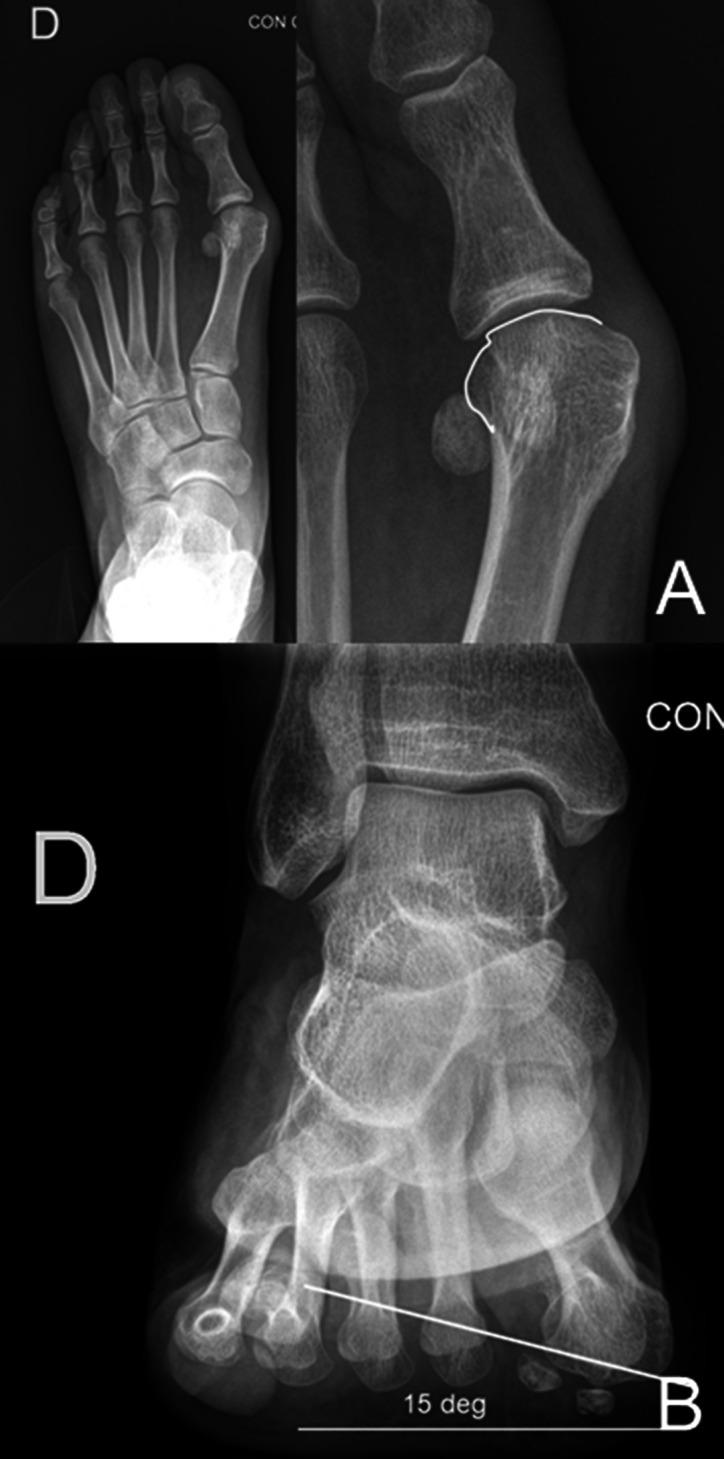

Hallux valgus deformity is a multiplanar deformity, where the rotational component has been recognized over the past 5 to 10 years and given considerable importance. Years ago, a rounded shape of the lateral edge of the first metatarsal head was identified as an important factor to detect after surgery because a less rounded metatarsal head was associated to less recurrence. More recently, pronation of the metatarsal bone was identified as the cause for the rounded appearance of the metatarsal head, and therefore, supination stress was found to be useful to achieve a better correction of the deformity. Using CT scans, up to 87% of hallux valgus cases have been shown to present with a pronated metatarsal bone, which highlights the multiplanar nature of the deformity. This pronation explained the perceived shape of the metatarsal bone and the malposition of the medial sesamoid bone in radiological studies, which has been associated as one of the most important factors for recurrence after treatment. Treatment options are discussed briefly, including metatarsal osteotomies and tarsometatarsal arthrodesis.

拇外翻畸形是一种多平面畸形,其中旋转成分在过去 5 到 10 年中得到了认可,并受到了相当大的重视。多年前,人们发现第一跖骨头外侧缘的圆形形状是术后检测的一个重要因素,因为较不圆的跖骨头与较低的复发率相关。最近,跖骨的内旋被认为是跖骨头呈圆形的原因,因此,旋前应力被发现对实现畸形的更好矫正很有用。使用 CT 扫描,高达 87%的拇外翻病例显示出跖骨的内旋,这突出了畸形的多平面性质。这种内旋解释了在影像学研究中所感知的跖骨形状和内侧籽骨的错位,这被认为是治疗后复发的最重要因素之一。简要讨论了治疗选择,包括跖骨截骨术和跗跖关节融合术。